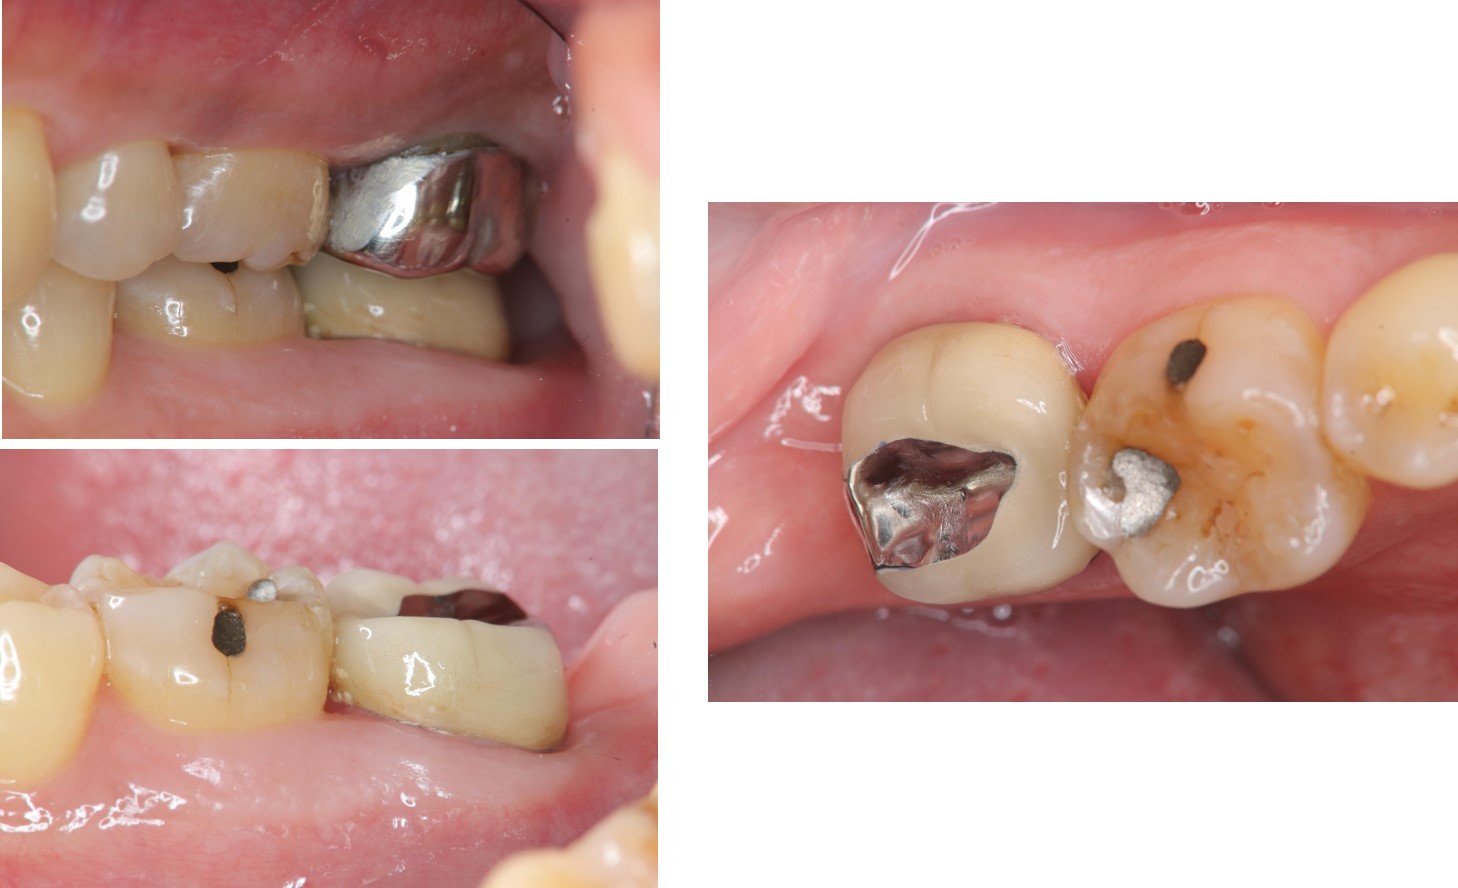

微金屬的金屬燒付瓷牙

治療後,咬合牙周良好

治療後,假牙密合度良好

術前、術後比較